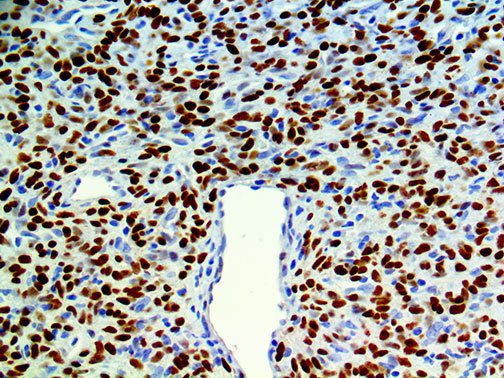

The first cytokines released are interleukin 1β (IL-1β) and tumor necrosis factor-α (TNF-α), which attract a variety of circulating white blood cells (WBCs) to the infection site, including neutrophils, monocytes, macrophages, and natural killer (NK) cells. This response, along with the antipathogenic chemicals released by these cells (i.e., complement), comprise the innate immune response. These cells directly attack the invading pathogen and also release additional cytokines, chief among them interleukin-1 and 6 (IL-6). IL-6 is essential for invoking the adaptive immune response, which calls T-cells, B-cells, and T helper (Th) cells to the infection site. IL-6 also stimulates further recruitment, proliferation and activation of macrophages.

It is the ICU physician who is most likely to witness one of the deadliest manifestations of the abnormal immunological response, the cytokine storm syndrome (CSS). This response is also referred to by some as the cytokine release syndrome (CRS). CSS is characterized by continuous activation and expansion of macrophage and lymphocyte populations, which secrete large amounts of cytokines, causing the cytokine storm. This massive cytokine release is akin to hemophagocytic lymphohistiocytosis (HLH) disease, a syndrome characterized by initial unchecked and persistent activation of cytotoxic T lymphocytes and NK cells.

Clinical and laboratory manifestations of HLH include fever, enlarged liver and/or spleen, neurologic dysfunction, coagulopathy, liver dysfunction, cytopenias (i.e., low levels of erythrocytes, leukocytes, and/or platelets), hypertriglyceridemia, hyperferritinemia, hemophagocytosis, and eventually diminished NK cell activity as the immune system becomes progressively paralyzed. HLH can be familial (primary HLH) or secondary to another disease process (sHLH), such as rheumatic disease, in which it is referred to as macrophage activation syndrome (MAS, characterized by elevated ferritin).